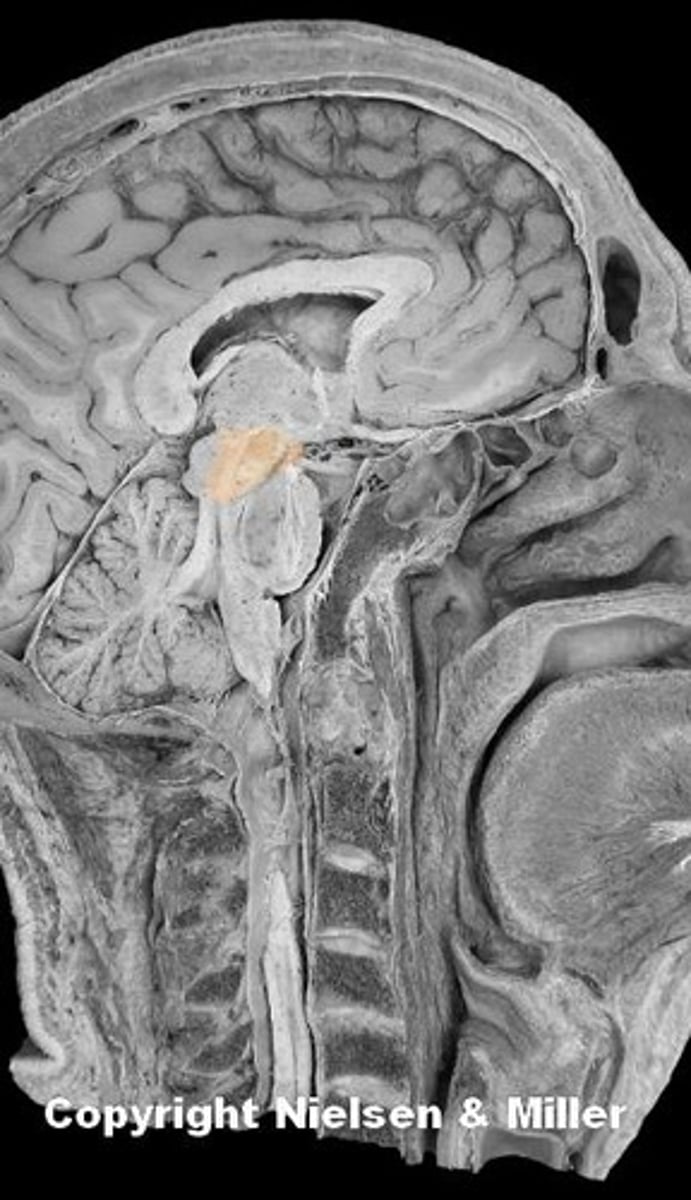

brain

cerebellum

cerebral hemispheres

cerebrum

fourth ventricle

hypothalamus

medulla oblongata

midbrain

pons

arachnoid mater

dura mater

pia mater